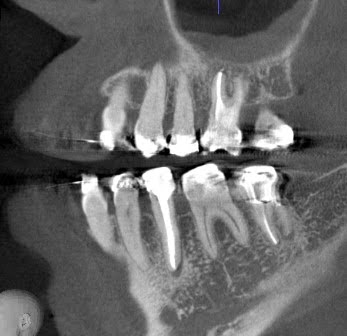

症例写真について

では、赤坂さくら歯科クリニックでの写真を見てみましょう。

以下の写真で治療前の写真ですが、上顎の6番の大きな根尖病変が上顎洞にまで波及しています。

上顎洞の白い不透過像(白く曇った像)も大きく見えています。

そして、治療後3ヶ月、根尖病変がなくなり、根尖の骨が治癒してきています。

上顎洞の白い曇った像も小さくなってきています。